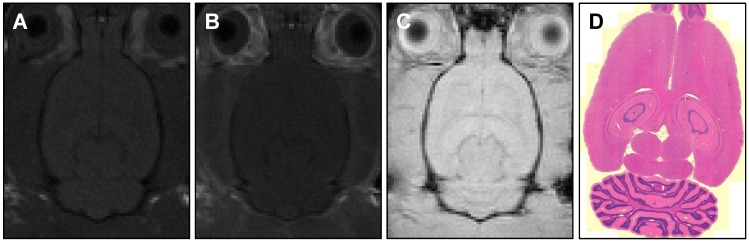

Figure 7.

MR images of (A) pre-treatment (T1-weighted) and (B, C) post-treatment (T1-weighted, T2*-weighted) axial slices showing no detectable BBB-opening or damage. Histology sections (D) with H&E staining and 5 μm slice thickness also confirm no tissue damage.